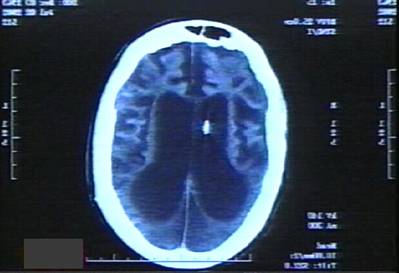

I just looked at her CT scan, and I'm truly amazed that this has gone on for so long. I've dealt with these issues before, and I've never seen them get to this point. A brain CT that looks like hers, is not only tragic, it's comical.

She has no cerebral cortex. Most of her brain has atrophied from the hypoxic insult, and essentially, she survives because her brainstem is still functional. This image, along with her flat eeg (not surprisingly, she has no cortex), would have been far more than enough evidence to "let her go", where I worked in an ICU.

I wonder how forceful the doctor's were with the parents. Obviously, they are at fault for allowing this travesty to continue for so many years.

Compare the following two images. Any moron can see the difference.

Truly sad.Experienced Community organizer. Yeah, let's choose him to run the free world. It will be historic. What could possibly go wrong...